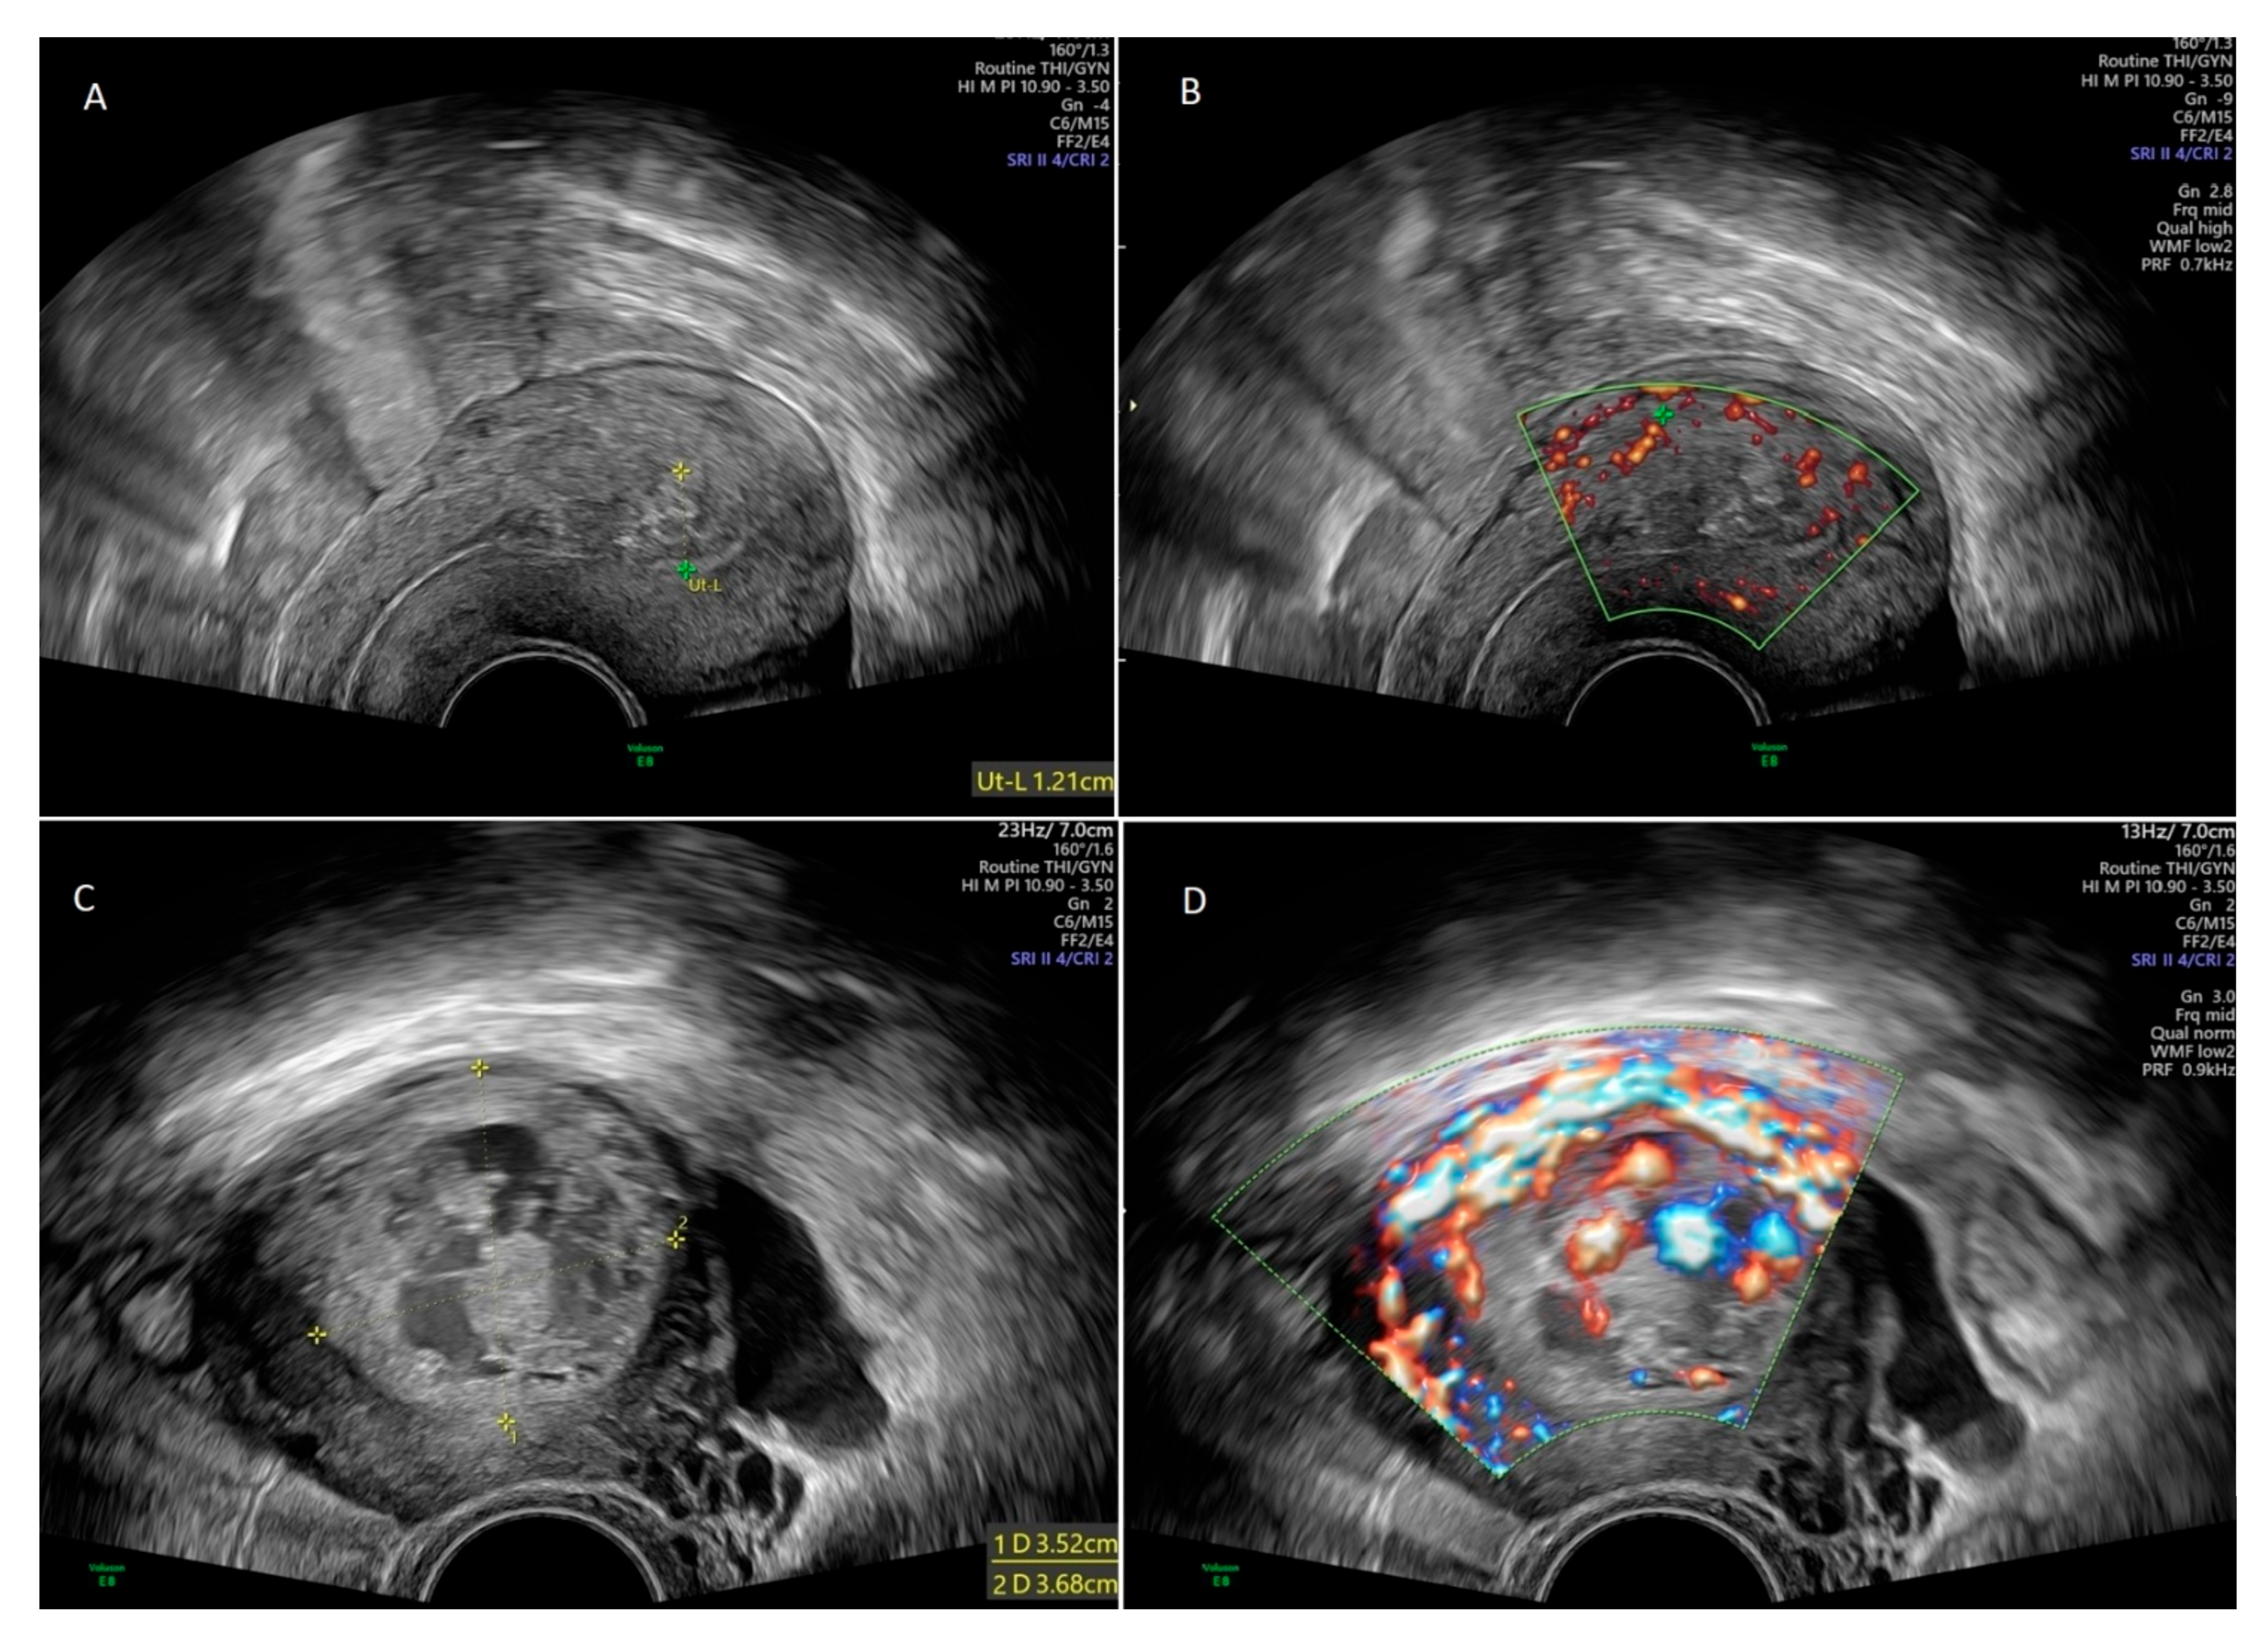

The diagnosis of RPOC was established based on clinical symptoms such as abnormal bleeding and transvaginal ultrasonography supplemented with color Doppler imaging. Sonographic criteria for RPOC included the presence of a heterogeneous intracavitary, predominantly hyperechoic focal mass, with or without increased vascularity [2]. Hypervascularity was classified based on color Doppler indices (color score 3 or 4). Transvaginal ultrasound in two RPOC cases are shown in Figure 1: one with minimal vascularity of the lesion and one case with highly vascular RPOC.

Figure 1. Transvaginal ultrasonography in 30-year old female with retained products of conception (RPOC) (A). Color Doppler ultrasound in the same patient showed minimal vascularity of the lesion (B). Transvaginal ultrasonography in 31-year old female with RPOC (C). Color Doppler ultrasound in the same patient showed hypervascularity of the lesion (D).